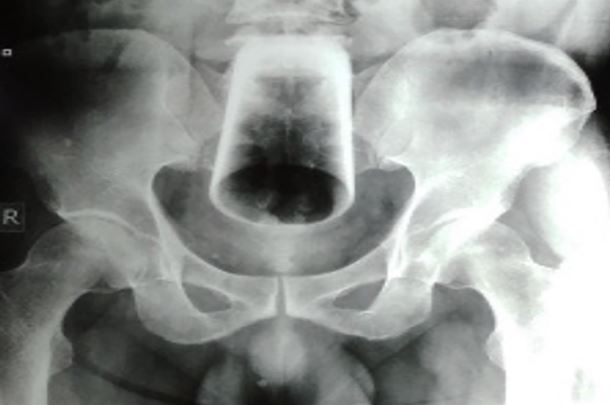

After an X-ray was done, doctors tried to remove it but couldn’t get a grasp on the glass as it was inverted.

“Milking was attempted to deliver the glass through the an*s, but this was unsuccessful as the glass was high up, inverted and tightly wedged,”

the journal explained.